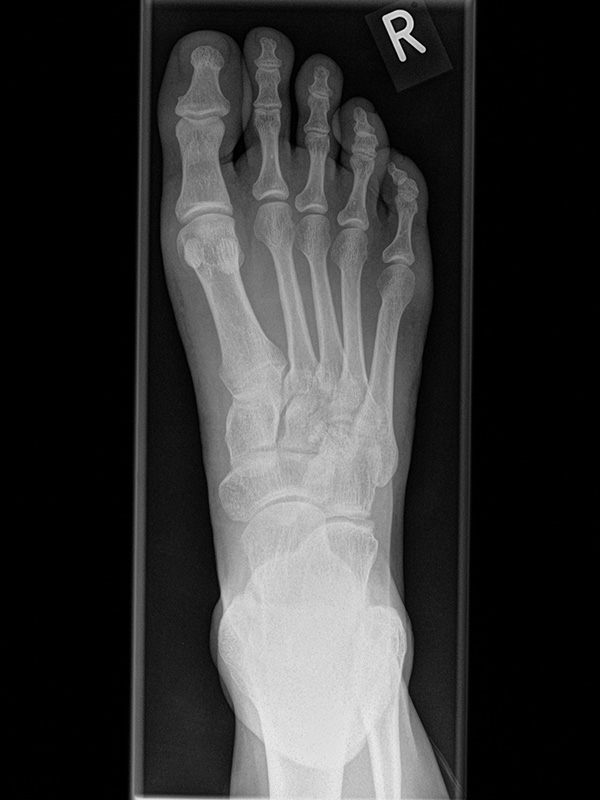

Fuß dp (dorsoplantar) mit Belastung

Positionierung:

• Der Patient steht unter gleichmäßiger Gewichtsbelastung auf beiden Füßen.

• Die Fußachse ist nach vorne gerichtet.

• Die Kassette liegt unter dem zu röntgenden Fuß.

• Der Zentralstrahl wird auf das Tarsometatarsalgelenk II zentriert.

• Die Röntgenröhre ist 15° vertikal gekippt.

• Anmerkung: Technisch lässt sich die Röhre beim stehenden Patienten nicht in 0° über dem Fuß positionieren. Eine Kippung der Röhre um 15° erlaubt darüber hinaus eine bessere Einsicht in die tarsometatarsalen Gelenke.

Kennzeichen des Röntgenbildes:

• Standardabbildung des Fußes zusammen mit der belasteten seitlichen Aufnahme und der unbelasteten Schrägaufnahme.

• Die belasteten Aufnahmen liefern relevante Informationen zur Fußstatik und sind die Grundlage aller achskorrigierenden Eingriffe an Vor- und Rückfuß.

• Sämtliche Winkelbestimmungen beziehen sich auf belastete Aufnahmen.

Besondere Bemerkungen zum Beispielbild:

• Schwere Hallux valgus Deformität.

• Die Sesambeine sind luxiert, ebenso das Großzehengrundgelenk. Luxation des Metatarsophalangealgelenks II.

• Degenerative Veränderungen der tarsometatarsalen (TMT) Gelenkreihe, betont TMT II und III.

Zur Vollansicht und zum Lesen der Bildbeschreibung bitte die Bilder anklicken.